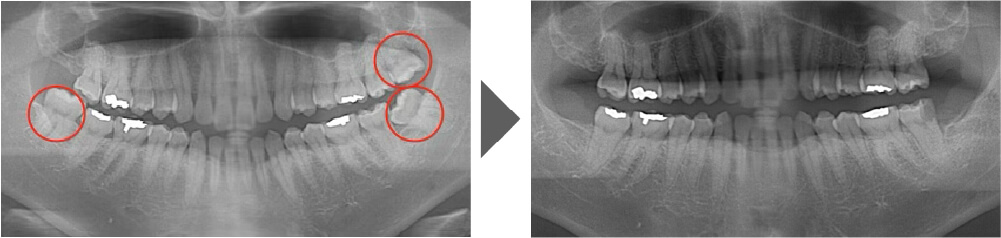

抜歯症例②

しっかり生えており、非常に磨きづらく虫歯のリスクの高い歯です。 上を2本とも抜歯しました。

【抜歯所要予約時間】

各15分

(麻酔の時間があるので処置自体はもっと短いです)